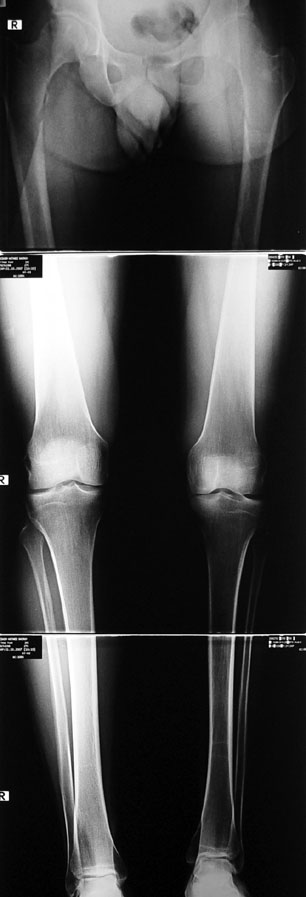

Bu Bacak Kısalık tipi bir kırığın kısalmış pozisyonda kaynaması ile oluşur. Bir çok vaka yetişkinlerde görülür ve sadece bir uzatma ile tedavi edilebilir. Ek deformiteler de aynı anda düzeltilebilir. Bu hastaların çoğu çivi üzerinden uzatma veya tam implante edilen çivi ile tedavi edilebilirler.

Vaka 4